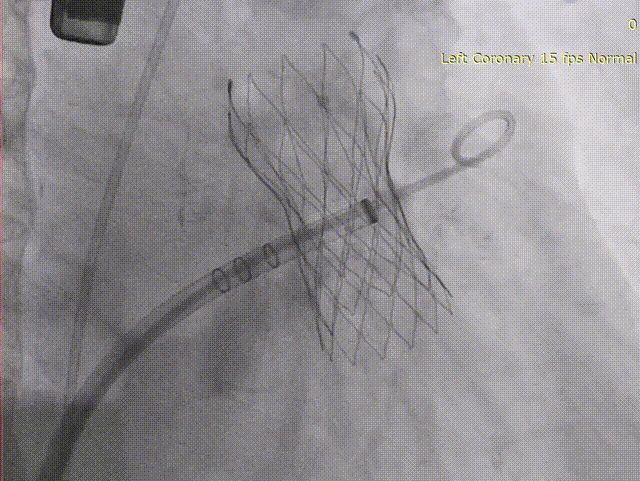

退鞘形成FLX BALL

WATCHMAN FLX™释放